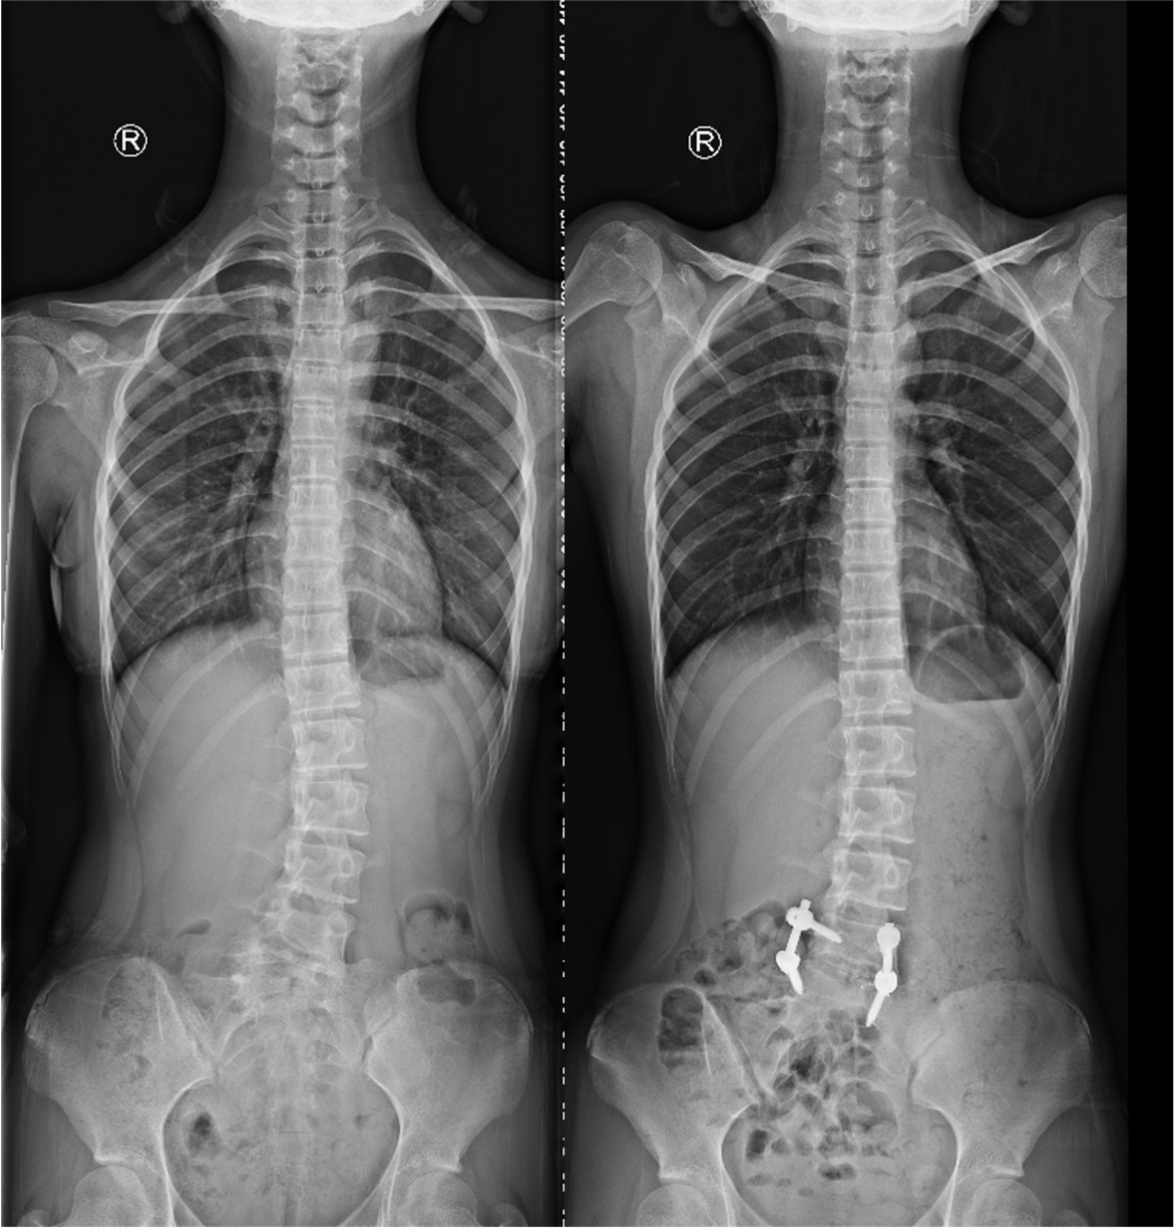

患者小王,是个14岁的小姑娘,身高1.65米,亭亭玉立,聪明可爱。1年前小王的父亲发现女儿走路时有高低肩,在当地检查拍片显示小王患有先天性脊柱侧弯畸形,当地医院建议其赴上级医院就诊手术。小王的父亲曾因先天性髋关节发育不良接受过手术,自身的手术经历使他一直犹豫是否让女儿接受手术。然而女儿的高低肩越发明显,作为父亲的他觉得不能再纠结了,于是带着小王来到了我院骨科姜为民主任门诊。

姜主任为小姑娘做了详细的体格检查,仔细阅读了影像资料后告知小王的父亲,孩子患的是一种第5腰椎先天性半椎体畸形而导致的腰椎侧弯畸形,采取手术方式干预迫在眉睫,否则畸形将会进一步加重。患者家属之前听说这种矫形手术切口很大,还需要打上十几个钉子,一直十分犹豫。看着患者父亲那焦急的神情,姜主任笑着安慰道:我们只需要采用相对小的手术把半椎体切除,再做适当的矫形即可。其余的部分畸形会随着生长发育自行矫正。在姜主任的耐心解释下,家属悬着的心终于放了下来,办理住院登记手续后不久顺利入院骨科病房。

入院进一步完善各项检查后,姜为民主任再一次对小王的影像资料进行了全面的研究,同时与团队成员商讨制定详细的手术方案。计划首先经后路切除L5半椎体,然后行椎间盘摘除凹侧椎间隙撑开矫形,再置入融合器行椎间融合,最后行短节段椎弓根内固定,以尽可能小的代价取得较为理想的效果。手术当日,姜主任熟练的通过截骨、置钉、撑开矫形、植骨融合等操作,顺利完成了手术。术后,患者小王恢复良好,术后影像检查显示半椎体已完全切除,矫形效果满意,手术非常成功。